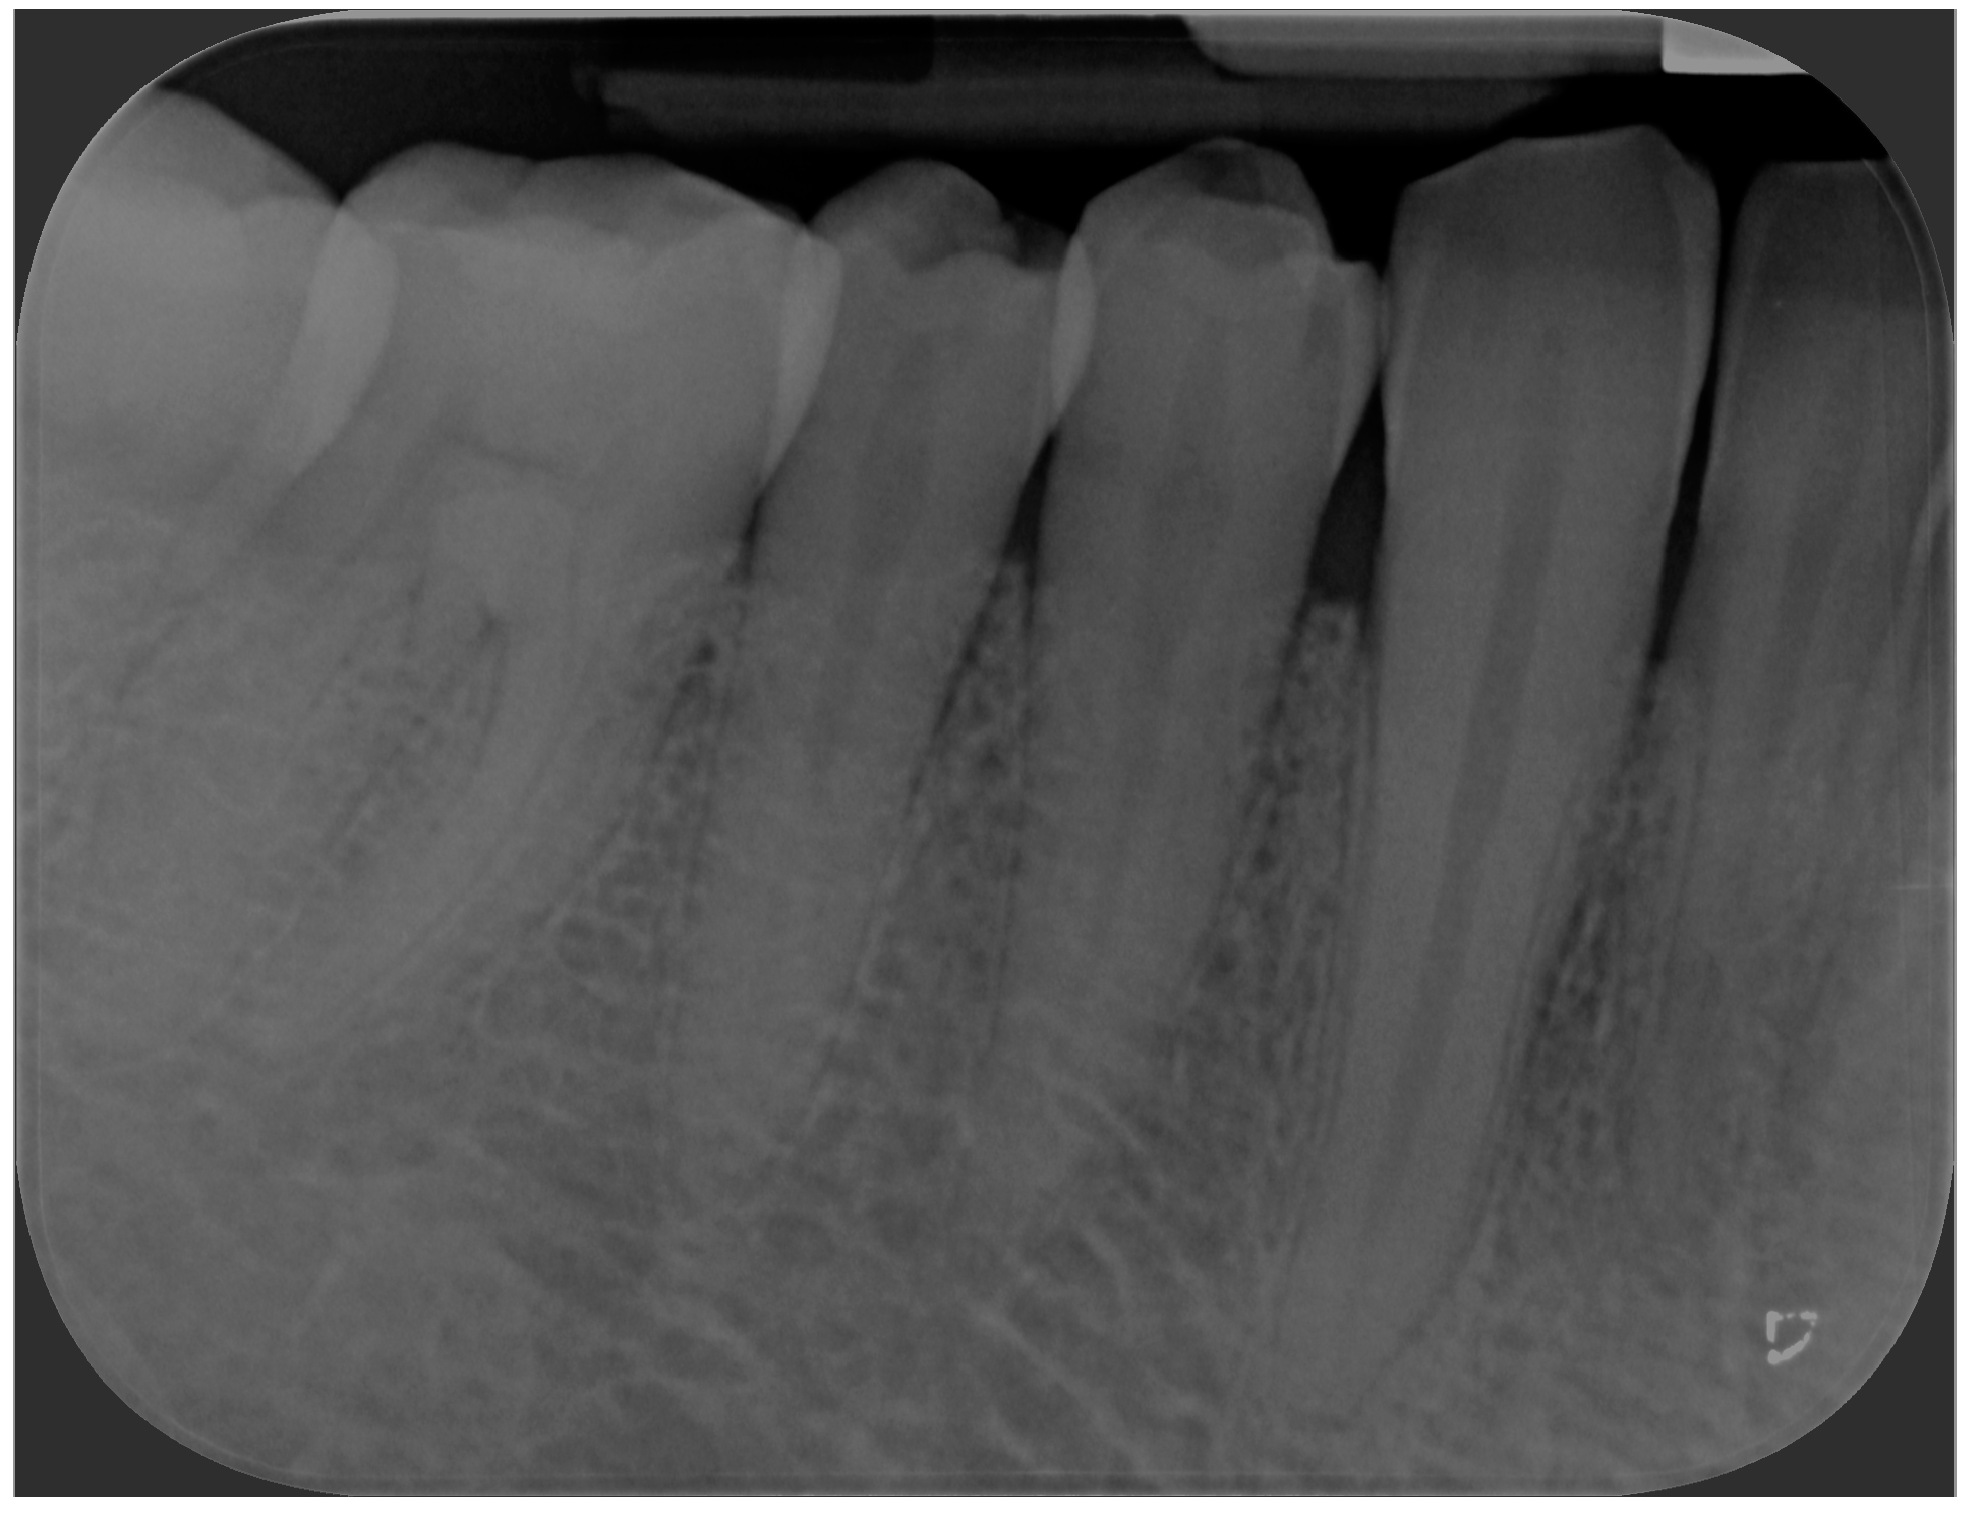

Case Presentation